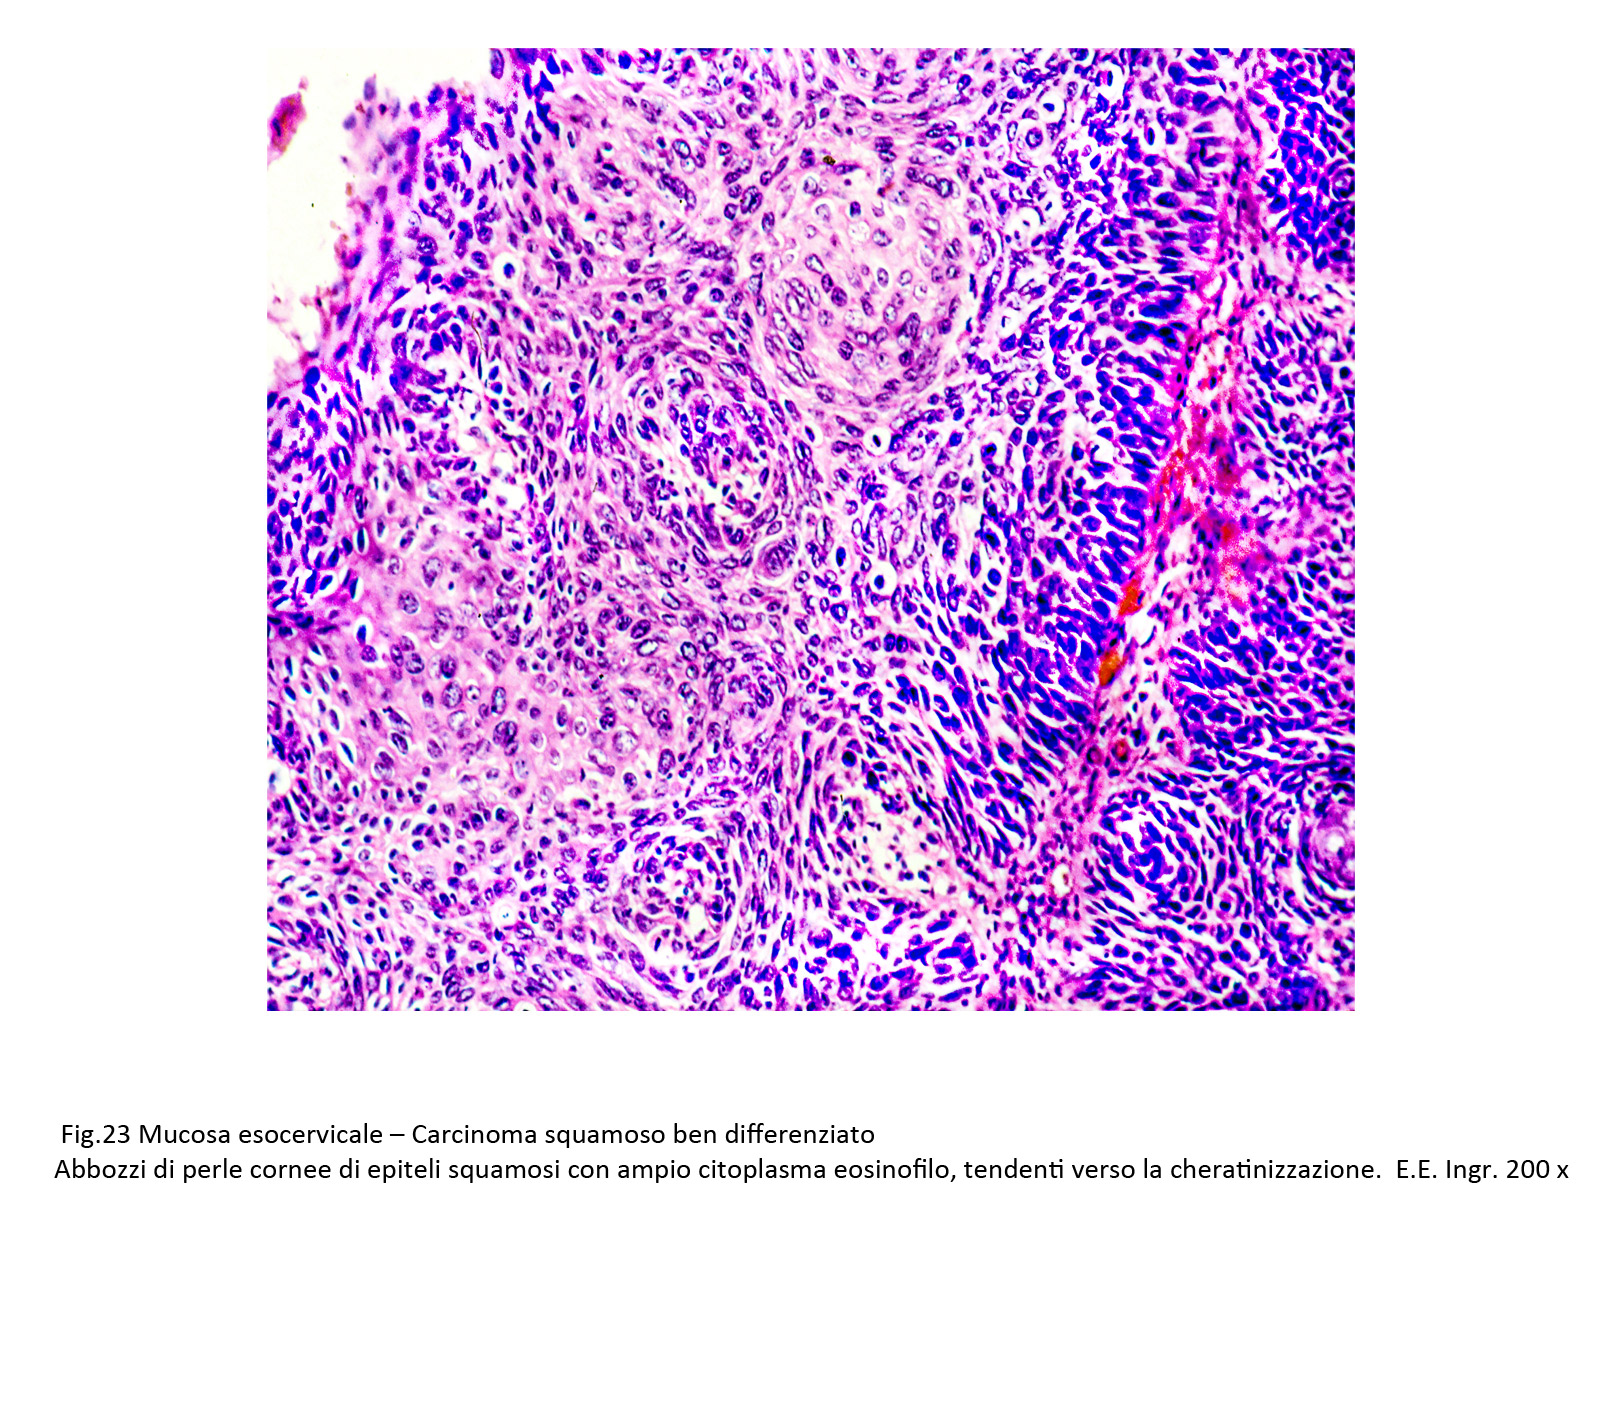

- 1. Carcinoma squamoso ben differenziato

La neoformazione è costituita da una popolazione epiteliale iperdensa; questa è formata da epiteli squamosi disposti astrati piani ma privi di coesione intercellulari; i singoli elementi hanno ampio citoplasma acidofilo e contengono al centro un voluminoso nucleo ipercromatinico.

La variante con abbozzi di perle cornee non cheratinizzate è costituita da elementi pleomorfi che si dispongono a fasci o in modo solido e tendenti a formare strutture a strati concentrici; molto spesso questi aggregati sferoidali sono occupati da epiteli squamosi in corso di cheratinizzazione.

Fig.22

Fig.23